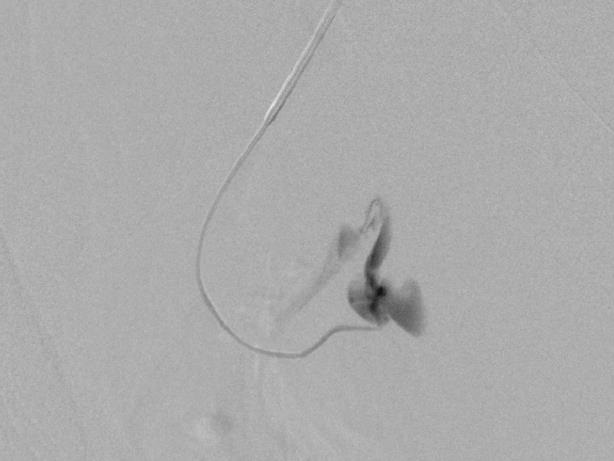

末端动脉栓塞:医源性肾损伤-移植肾活检

活检后动脉瘤破裂 |

微导管在载瘤动脉末端 |

载瘤动脉末端栓塞 |

Coil=3 |